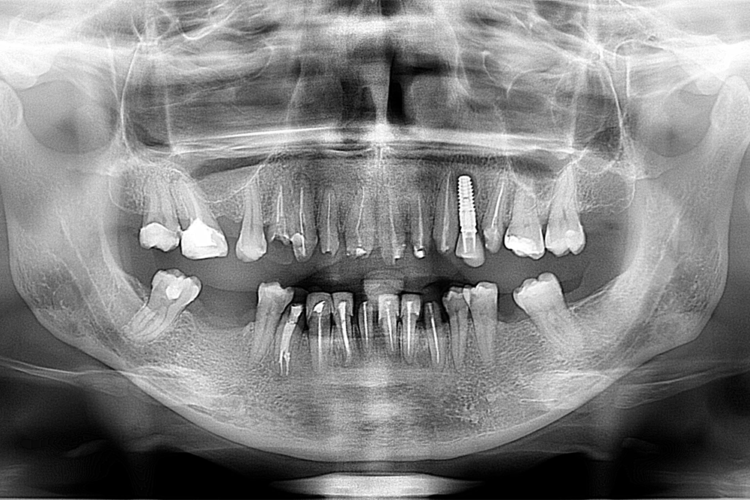

Caz reabilitare orala totala cu fatete si coroane

Pacienta in varsta de 38 ani, s-a prezentat cu plombe si lucrari dentare vechi si tratamente incomplete. S-au reluat toate tratamentele endodontice la microscop refacandu-se bonturile pentru structura protetica. S-a optat pentru varianta cea mai estetica si eficienta prin aplicarea de coroane si fatete dentare ceramice de tip hibrid (zircon bio star+hera ceram zirconia).